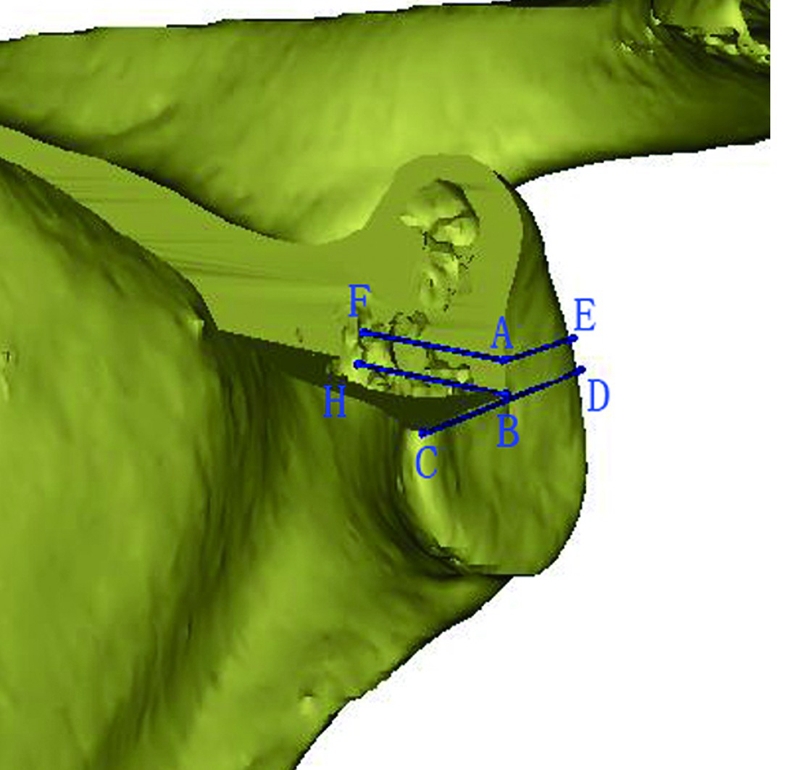

Codsi等将61个肩胛骨样本进行CT扫描并进行三维重建,依据肩胛盂上下径将其分为6组,获取不同分组肩胛盂体部前后壁骨内边界,描绘出不同分组肩胛盂体部三维形态;依据肩胛盂上下径将不同分组的肩胛盂体部三维结构缩放为常规大小对三维形态进行比较,发现在所研究正常人群中,肩胛盂体部内部三维结构一致。肩胛盂体部内部形态的统一性,可指导关节假体设计、重建,帮助理解肩关节发育不良及关节退变性疾病的发生,但Codsi等对肩胛盂穹隆的三维结构并没有定量研究,临床应用有一定的局限性。Bicknell等对72个肩胛骨标本行CT扫描,测量了肩胛盂中心前后径、上下径,认为肩胛盂穹隆内部结构相对一致,冠状面为矩形、水平面为三角形的假体更符合肩胛盂体部的解剖学形态。肩胛盂体部男性解剖学参数较女性大,存在显著的性别差异,但肩胛盂体部内部形态男女未见差异。除此之外,Bicknell等还测量了肩胛盂中心的上下径、前后径等解剖学参数; 但是肩胛盂体部解剖结构复杂,单以中心测量很难反映其总体解剖学形态。Keisuke等应用三维重建技术重建肩胛盂体部的三维解剖,进行定量分析,测量了以肩胛盂中心22×12mm范围内间隔2mm的肩胛盂体部深度和肩胛盂中心上下4mm肩胛盂体部的前后径,使局部复杂的结构可视化、定量化,并对反肩置换假体设计提供参考(图7)。

图7 肩胛盂体部深度、前后径的测量示意图。应用CT数据对肩胛骨进行三维重建(移除了肩胛盂体部前上部分),以肩胛盂上下极、前后缘的连线建立坐标系,测量肩胛盂体部深度和肩胛盂体部前后部宽度。图中线段AF、BH为肩胛盂中心和其上2mm肩胛盂体部深度;线段BC为肩胛盂体部前部宽度;线段AE、BD为肩胛盂体部后部宽度。线段AE、BD之间的距离为2mm,可对肩胛盂体部形态进行定量化分析